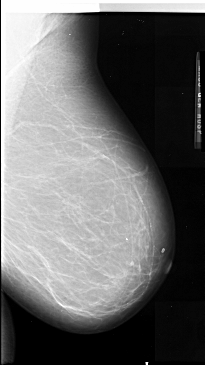

A_1090_1.RIGHT_MLO

RIGHT_MLO LINES 6571 PIXELS_PER_LINE 3676 BITS_PER_PIXEL 16 RESOLUTION 42 NON_OVERLAY